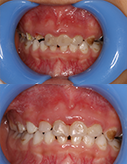

儿牙修复---根管治疗+树脂修复

孩子牙齿龋坏疼痛大哭 修复完毕后破涕为笑